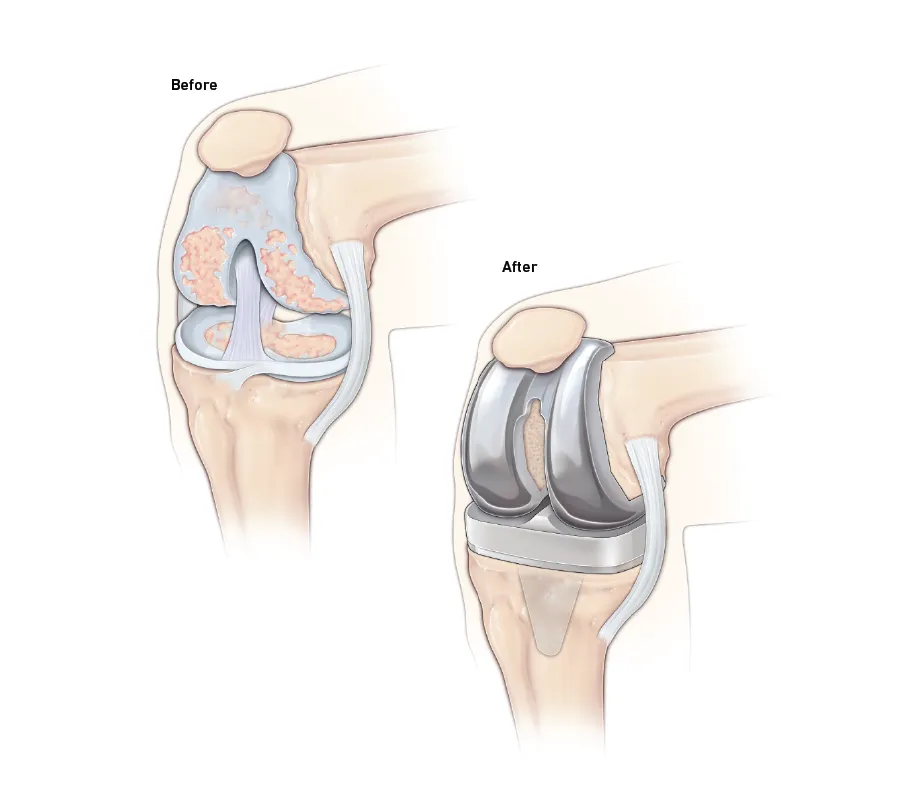

When arthritis intrudes; however, the protective layer of cartilage in the knee gradually wears away, becoming frayed and rough, making it painful to move the joint. The knee then becomes unable to effectively cushion the body from impact and stress. The result is a painful joint that can gradually hamper your quality of life, reduce your independence, and make it hard – or impossible – to do the things you want to do.

Total Knee Replacement is the surgical removal of the damaged joint and replacing it with an artificial joint that is attached to the thigh bone (femur) and the shinbone (tibia).

This is known as a prosthesis or an implant. In most cases, bone cement is used to fix the artificial joint to the thigh and shinbone.

We remove the damaged cartilage and bone from the knee to replace with metal and plastic molded implants. The new implants make the joint movements smooth enabling them to work freely and relieving you of the pain caused earlier.